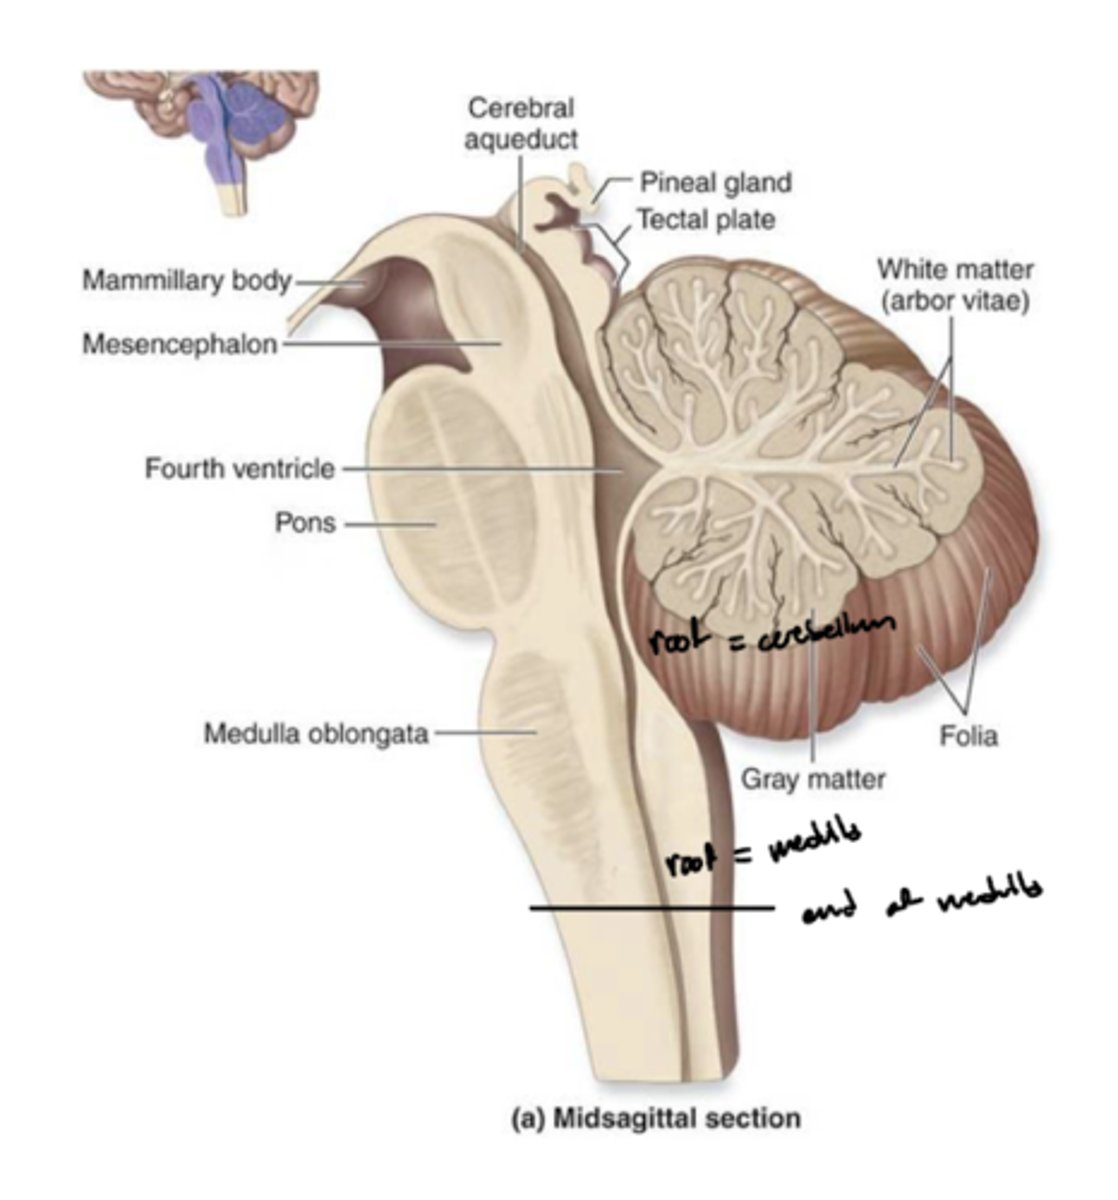

What are the structures of the brainstem?

1. mesencephalon (midbrain)

2. pons

3. medulla oblongata

What is the tectum?

roof of the midbrain

What is the tegmentum?

floor of midbrain

What are the fibers of the tegmentum?

ascending fibers

What is the crus cerebri?

part of the cerebral peduncles which contain descending tracts

What are the fibers of the crus cerebri?

descending fibers